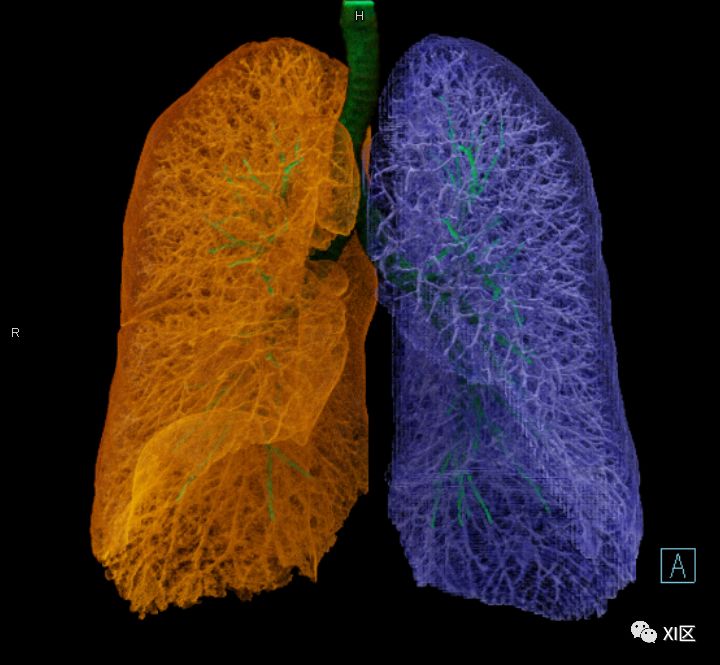

气管支气管树与两肺融合显示

左肺借斜裂成上、下两叶;右肺借斜裂和水平裂成上、中和下叶三叶。